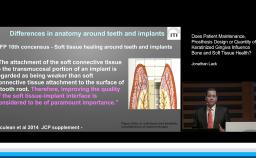

- recognize that patients with a history of periodontal disease demonstrate a higher risk of peri-implant diseases

- identify risk factors for implant therapy which may affect treatment outcomes